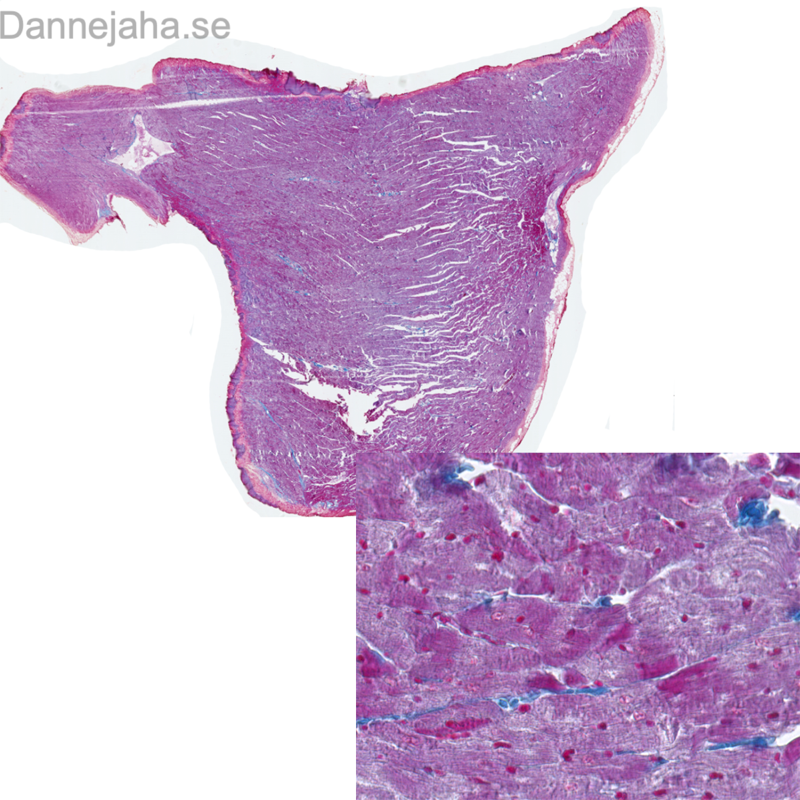

| 3:E:1 | Hjärtmuskel | Hjärta | ![]() ![]() ![]() ![]() ![]() ![]() |